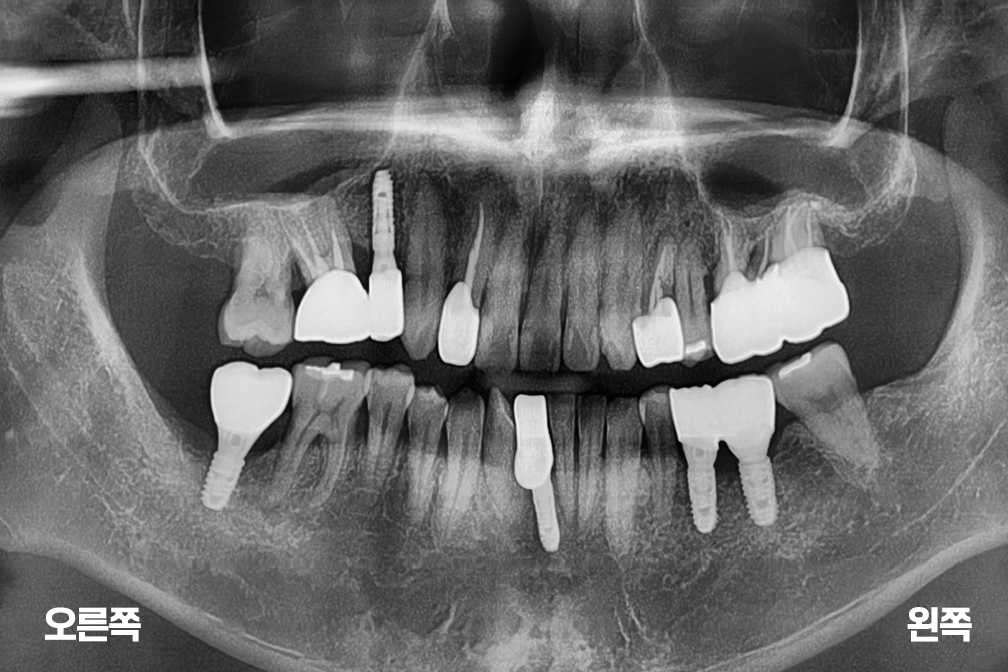

임플란트 오른쪽 위 앞니 임플란트 + 아래 양쪽 임플란트 수술

Before 2025년 8월 16일